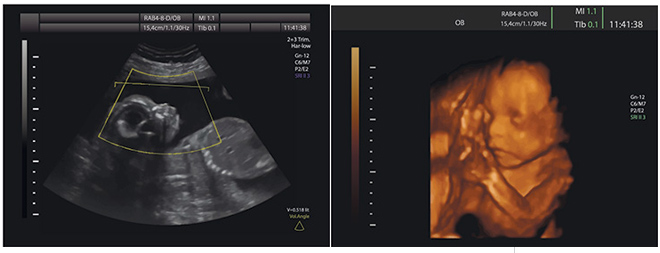

Late pregnancy scanning

The main reason for scanning at this late stage is to monitor foetal growth. This is done by measuring the circumference of the baby’s head, the length of the femur and the size of the abdomen. If there is any concern regarding foetal wellbeing, a cardiotocograph (CTG) will be done together with an assessment of foetal movements.